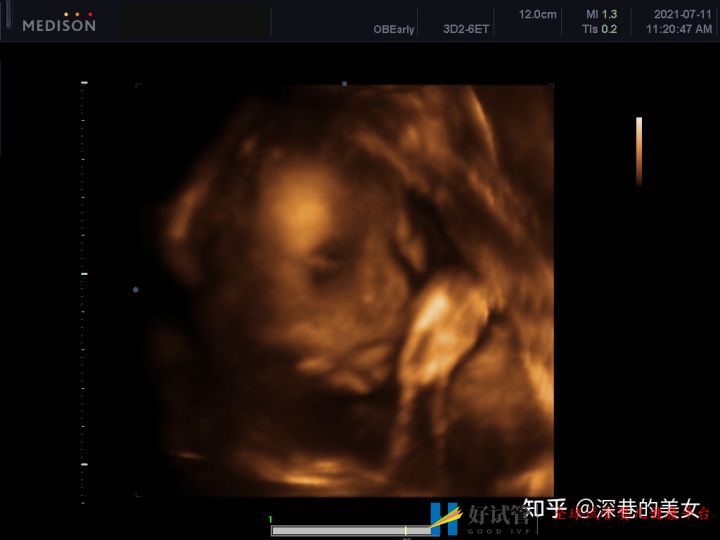

满心期待熬到24周了,以为可以去跟小家伙见一面了。结果我们医院是三级B超,没有四维彩超。所以就没有网上那种脸部照片。心里好失落啊。毕竟期待了那么久。虽然医生说着娃娃漂亮、下巴漂亮。但还是想看看。

没有忍住还是去私人医院给小家伙照了四维照片。

鼻梁的确高。哈哈